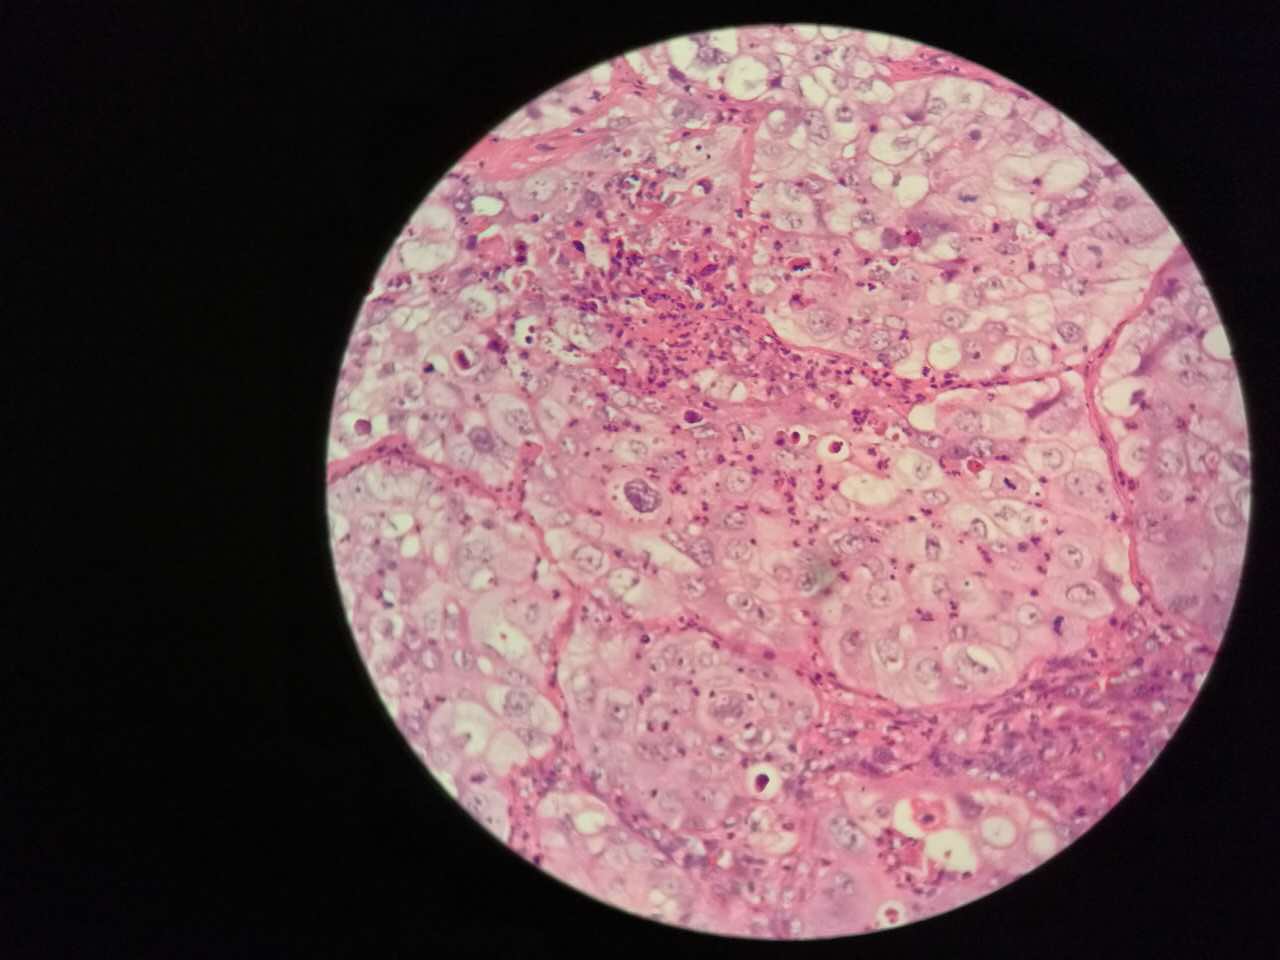

细胞外粘液湖

细胞外粘液是白色偏微红

这一幅的上方都是黏液湖

下方是正常肺泡

细胞内白颜色区是粘液,细胞外洋流样的也是粘液(湖)

黏液湖里可以飘着一些细胞,吞噬细胞及肿瘤细胞。

肿瘤细胞飘出去可以种植于肺泡上。

肿瘤细胞堆经常是离开的

中间这一团,整个都是飘过来种植长成这样

这在进展后期特别多见

早期飘散常很近